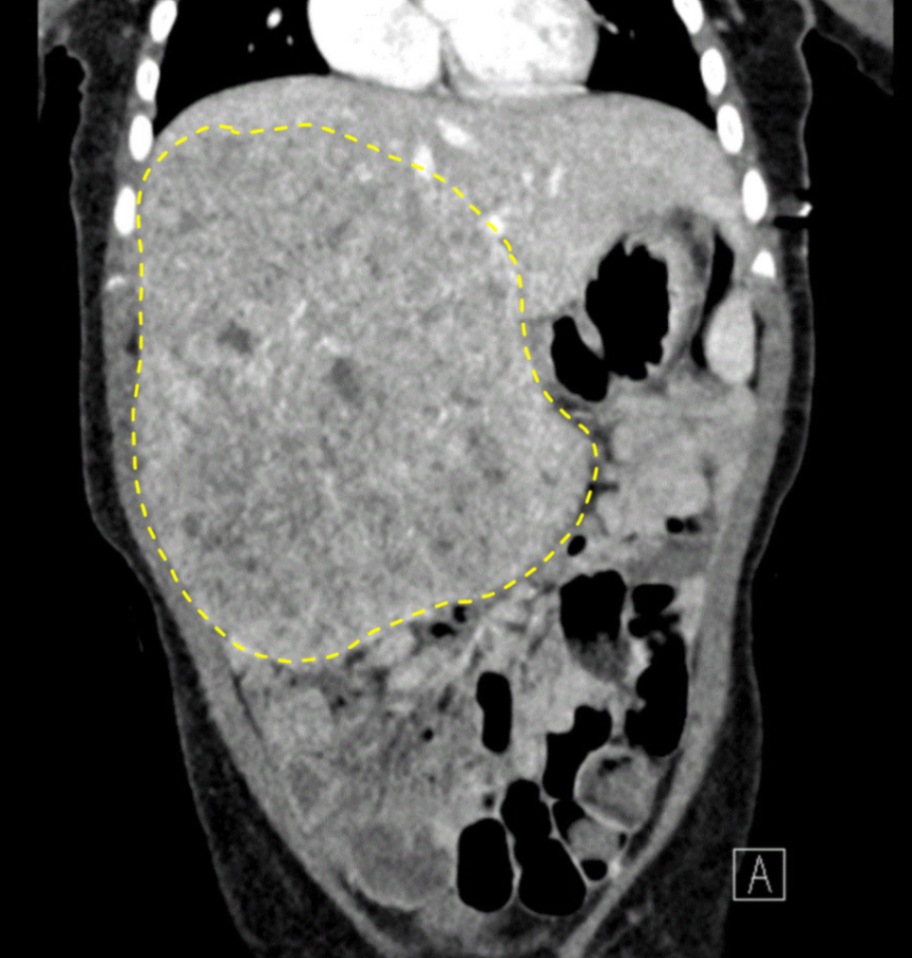

1세 남아가 3일 전부터 윗배에서 덩어리가 만져져서 왔다. 1개월 전부터 잘 먹으려 하지 않고 먹지 않아도 배가 불러 보이며 자주 보챈다고 한다. 혈압 150/90 mmHg, 맥박 90 회/분, 호흡 20회/분, 체온 37.0 ℃이다. 왼쪽에 비해 오른쪽 팔다리가 더 두꺼우며 오른쪽 윗배에서 손바닥 크기의 단단한 종괴가 만져진다. 검사 결과는 다음과 같다. 복부 컴퓨터단층촬영 사진이다. 치료는?

Img | CT: Large heterogenous mass lesion arising from right liver lobe |

• 소변 VMA는 정상으로 신경모세포종의 가능성은 낮고, CT에서 Rt. liver lobe에 크고 불균질한 종괴(large heterogenous mass)가 확인되어 간모세포종 진단에 결정적으로 부합한다.